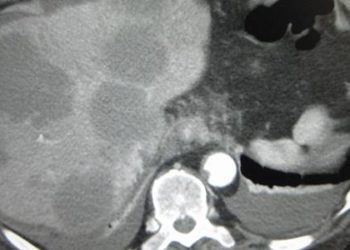

Study Rundown: In liver transplantation, nonanastomotic biliary strictures are a significant complication impairing new liver function. One mechanism is ischemia-perfusion injury, and previous clinical data suggested oxygenation through a machine perfusion machine may be protective against these injuries. As such, this study determined transplanted liver function compared between hypothermic oxygenated machine perfusion and static cold preservation. The study determined patients who received livers from the machine-perfusion had significantly reduced risk of nonanastomotic biliary strictures, postperfusion syndrome, and early allograft dysfunction. The incidence of adverse events was similar between both groups. A key limitation of this trial was that it lacked power along with follow-up time to detect an effect on overall survival and graft survival. Overall, hypothermic oxygenation through machine perfusion led to fewer biliary stricture complications and early graft failure without any significant increase in adverse events compared to static cold storage.

In-Depth [randomized controlled trial]: This was a multicenter, randomized, open-label trial of 160 patients. Patients undergoing liver transplantation from a donor after circulatory death were included in the study. Patients were excluded if the donor’s body weight was less than 40 kilograms. Patients were randomized in a 1:1 ratio to hypothermic oxygenated machine perfusion or static cold storage, respectively. The primary endpoint was the incidence of nonanastomotic biliary strictures. Nonanastomotic biliary strictures occurred less in the machine-perfusion group compared to the standard of care (hazard ratio [HR], 0.36; 95% confidence interval [CI], 0.14-0.94; P = 0.03). Furthermore, postperfusion syndrome (relative risk ratio [RR], 0.43; 95% CI, 0.20-0.91) and early allograft dysfunction (RR, 0.61; 95% CI, 0.39-0.96) were less in the machine-perfusion group compared to the standard of care. The number of treatments for the machine perfusion group was less by almost a factor of four compared to the control group. Reported adverse events were similar (treatment group, 644; control group, 694) and of similar distribution. In general, hypothermic machine oxygenation perfusion may become standard of care for liver donors after circulatory death given the improvement in transplant outcomes without significant adverse events.